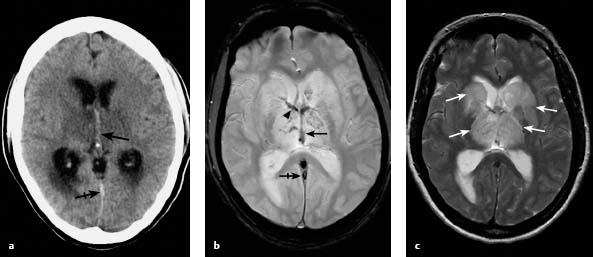

Дегенерация синуса

Дегенерация синуса 83 фото